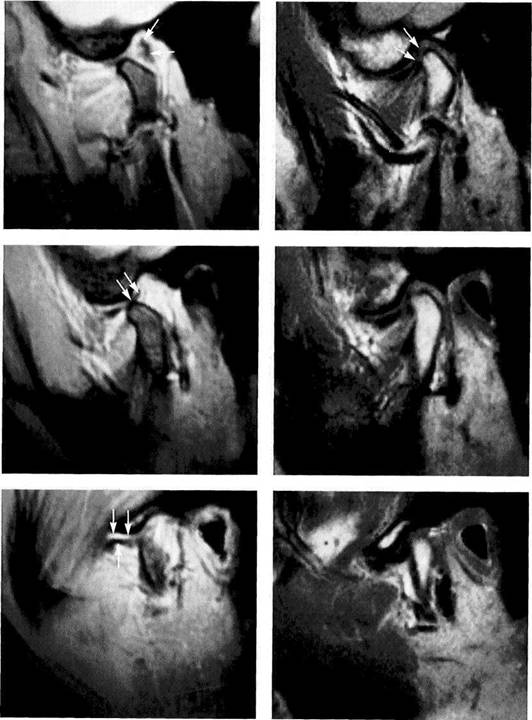

Misinterpretation of the Disk Position in the Sagittal Plane

Numerous studies have found an agreement rate of 80-95% between MR images and anatomical dissections of the tem­poromandibular joint regarding the disk position (Katzberg et al. 1988, Sander 1993, Tasaki and Westesson 1993). As described in earlier chapters of this book, the formation of a pseudodisk through fibrosis of the bilaminar zone is one pos­sible cause of misinterpretations of MR images (Katzberg et al. 1986, Drace et al. 1990). Other factors that can cause false evaluations of the disk position are signal-poor sections of tendon in the superior head (Beltran 1990, Bumann et al. 1992a) or inferior head (Bittar et al. 1994) of the lateral

pterygoid muscle. But also fibrosis, which reduces the signal intensity, in the anterosuperior part of the jont capsule can mimic an anterior disk displacement. The fundamental statement that "the imaging procedures must fit the clinical findings, and not vice versa" applies especially to an evalu­ation of the disk position in the temporomandibular joint. When findings disagree, inclusion of adjacent MRI slices in the analysis frequently resolves the question.

Tendon of the lateral

pterygoid muscle

Left: In this MRI of a 45-year-old man, the weak signal from the ten­don of the inferior head of the later­al pterygoid muscle creates an image (arrows) that could be misdi­agnosed as "an anteriorly displaced biconcave disk." Upon closer in­spection, however, the flattened disk can be seen lying between the condyle and articular eminence. Right: This slice made 3 mm farther medially shows a tendency to ante­rior disk displacement with fibrosis of the bilaminar zone. In this sec­tion the signal-poor tendon can no longer be seen.

Fibrosis of the anterosu-

perior portion of the joint

capsule

Left: Upon superficial inspection this MRI of a 48-year-old woman appears to show a complete anteri­or disk displacement (arrows). This appearance, however, is due to fi­brosis of the upper anterior part of the joint capsule.

Center: A correct evaluation reveals that the disk is in its normal posi­tion on the condyle (arrows).

Right: This slice 3 mm farther medi­al confirms the finding of a normal disk position (arrows).

Specific examination

sequences

Left: Left temporomandibular joint of a 15-year-old with a distinct ten­dency for anterior disk displace­ment (arrows; spin-echo [SE] tech­nique)

Right: Superficial inspection of the same joint imaged with a gradient echo technique (Flash 2D) could lead one to assume that the disk position is normal. In the correct in­terpretation, the true boundaries of the disk (arrows) and the fibrosed bilaminar zone (outlined arrow) are lying behind the pars posterior.